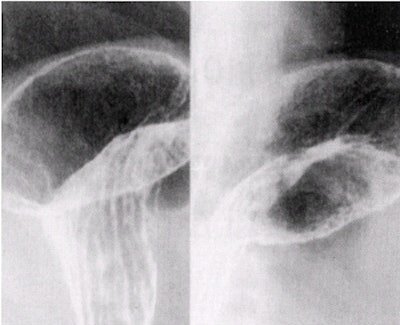

![]() |

| Stomach images in which the upper two images are obtained with compression. The bottom two images are superior body and fundus, which, being under the ribs, cannot be compressed. Image courtesy of Dr. Naveed Ahmad. |